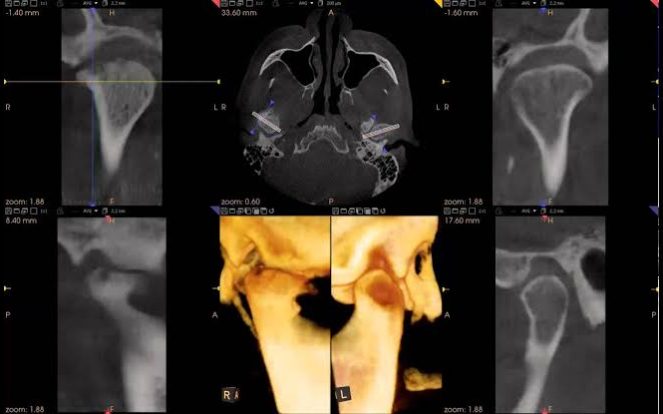

Temporomandibular eklem hastalıklarının kesin teşhisi için, TME’nin kemiksel bileşenlerinin bütünlüğünü ve birbirleri ile olan ilişkilerini değerlendirebilmelerini sağlayan, eklem hastalığının büyümesi veya ilerlemesinin doğrulanması ve tedavinin etkisinin değerlendirilmesinde kullanılan bir grafi yontemıdır.